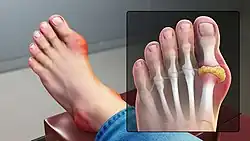

Gout is a form of arthritis caused by excessive uric acid production, resulting in urate crystals depositing in joints, particularly in extremities, such as toes.[48][49] Urate levels in the blood may increase from consuming purine-rich foods or from body factors affecting urate clearance from the blood, a topic remaining under study.[48]

Gout

In the early stages of gout, usually only one joint is affected; however over time, many joints can become affected. Gout most commonly occurs in joints located in the big toe, knee, and/or fingers.[49] During a gout flare, the affected joints often become swollen with associated warmth and redness. The resulting pain can be significant and potentially debilitating.[71] When one of these flares occurs, management involves the use of anti-inflammatories, such as NSAIDs, colchicine, or glucocorticoids.[72] In between gout flares, it is recommended that patients take medications that decrease the production of uric acid (i.e. allopurinol, febuxostat) or increase the elimination of uric acid from the body (i.e. probenecid).[72][73]

Gout has been associated with excessive intake of alcohol and food, such as red meat.[49] Thus, it is also recommended that patients with gout adhere to a diet rich in fiber, vegetables, and whole grains, while limiting the intake of alcohol and fatty foods.[49]